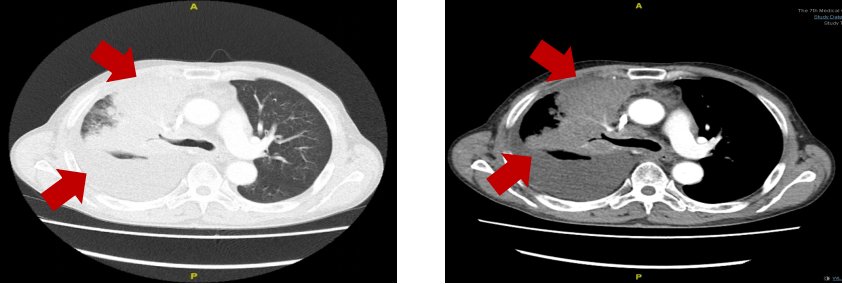

胸部增强CT:右肺中叶、肺门周围见大片软组织密度,强化不均匀,右肺支气管壁明显不规则增厚,管腔部分变窄、闭塞,纵隔内见多发肿大融合淋巴结,右侧

胸部增强CT:右肺上叶、中叶及肺门周围软组织密度影范围增大,纵隔内见多发肿大融合淋巴结,心包积液,右侧胸腔大量积液。